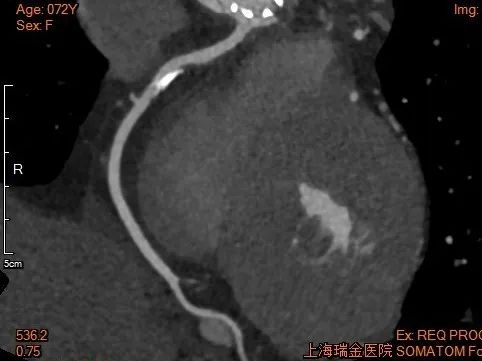

术后1w——冠脉CTA